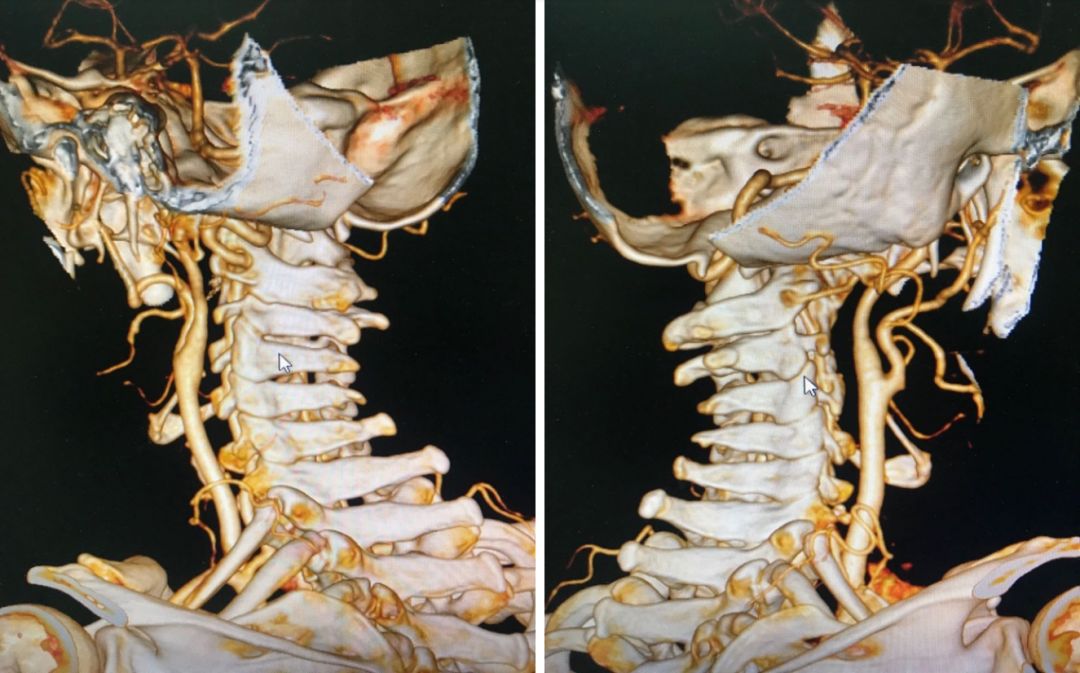

术前CTA显示双侧椎动脉走形异常。

(1)椎动脉走形,及其是否影响了侧方关节的松解。正如本例所示优势侧椎动脉直接在畸形的关节后方走形,术中需对椎动脉移位,才能完成关节间松解;

(2)椎动脉是否存在高跨,颈2椎弓根钉是否能植入。本例颈2椎弓根尚可,均植入螺钉;